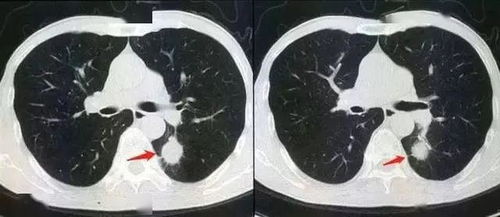

CT扫描通过精确的X射线束对人体进行扫描,能够获得高清晰度、高分辨率的图像。这些图像可以清晰地显示人体内部的器官和组织结构,对于诊断疾病具有重要意义。与X光相比,CT图像的分辨率更高,能够更准确地识别病变。

CT扫描具有卓越的密度分辨率,能够区分不同组织之间的密度差异。这对于诊断骨骼、软组织、血管等部位的病变具有重要意义。在X光检查中,由于密度分辨率较低,一些细微的病变可能无法被发现。